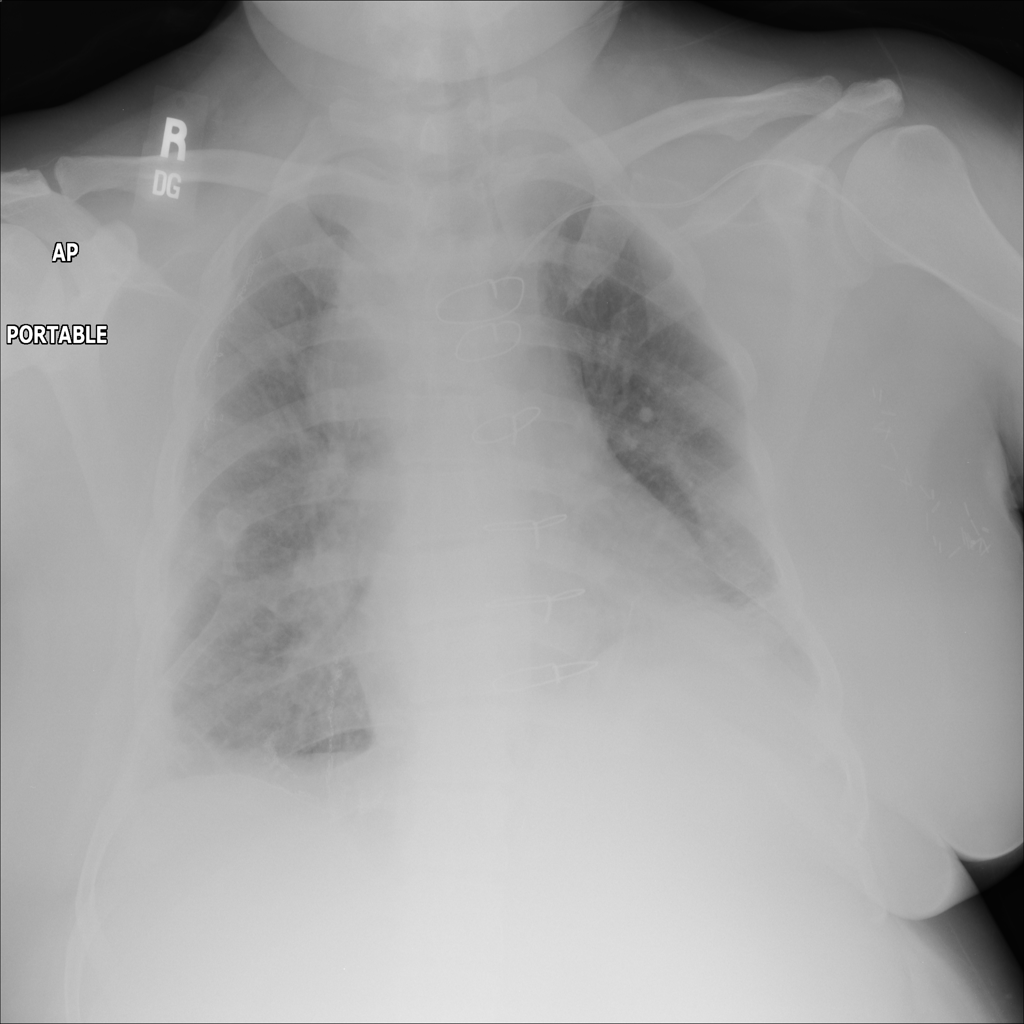

PAT-DB80 · IMG-001Atelectasis

PAT-DB80 · IMG-001

PA